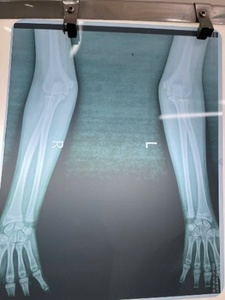

ILLUSTRATIVE IMAGES DEMONSTRATING THE FINDINGS AT 5-YEAR FOLLOW-UP

At 1 year of scheduled follow-up, the patient had resumed nearly all normal activities, including self-care and non-contact sports, with only a 10° terminal limitation of forearm pronation compared with the uninjured side. There was no recurrent dislocation, chronic pain, elbow deformity, or nerve palsy. Radiographs showed an anatomically aligned radiocapitellar line, confirming the success of annular ligament reconstruction.